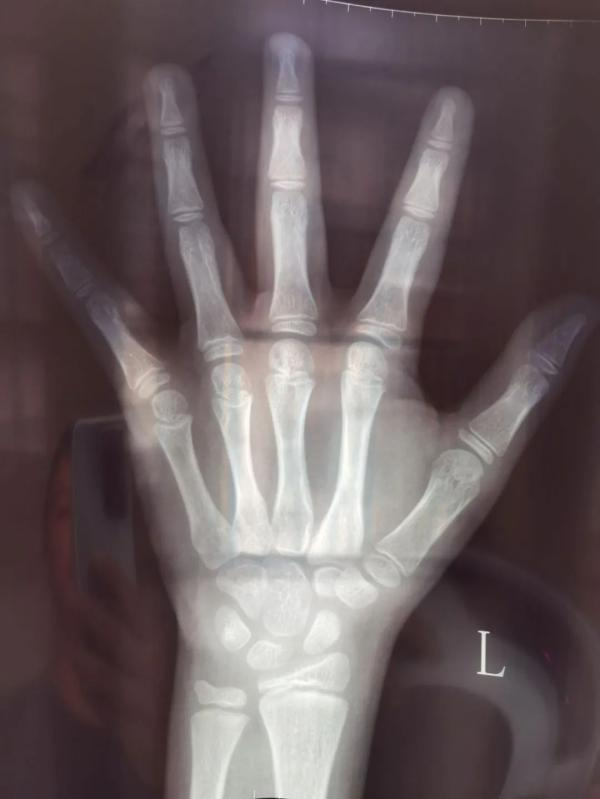

胡思云对自己拎着的那一沓片子和检查结果如数家珍:“这是x光骨龄片,这是脑袋的核磁共振片,这是子宫卵巢b超,这些是血常规、血糖、甲功检查和生长激素激发试验的结果……”